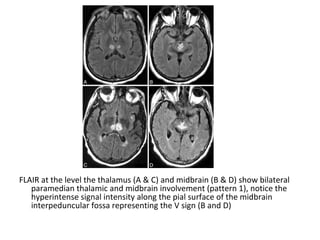

FLAIR at the level the thalamus (A & C) and midbrain (B & D) show bilateral

paramedian thalamic and midbrain involvement (pattern 1), notice the

hyperintense signal intensity along the pial surface of the midbrain

interpeduncular fossa representing the V sign (B and D)